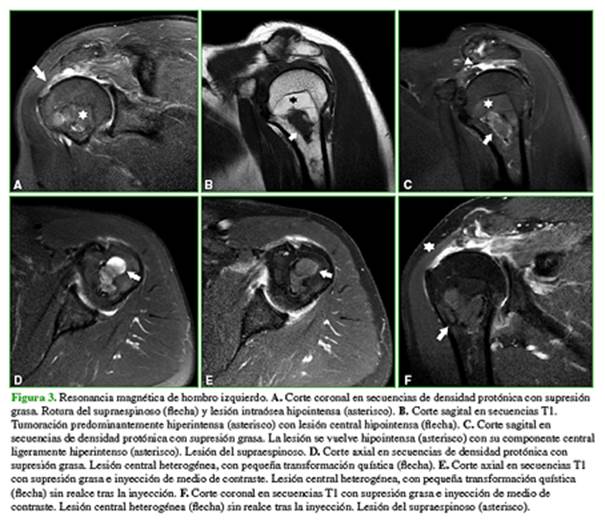

En la resonancia magnética de hombro izquierdo (Figura 3), se visualiza una tumoración en la región centromedular, metafisodiafisaria proximal. Predominantemente está conformada por una lesión hiperintensa en secuencias T1 e hipointensa en secuencias con supresión, rodeando un área esclerótica central hipointensa en todas las secuencias.

Tiene un borde definido a proximal y poco definido a distal. Tras la inyección del medio de contraste, no se observa realce de ninguno de los componentes de la lesión.

La articulación acromioclavicular presenta cambios degenerativos con disminución del espacio acromiohumeral. Se observa la rotura de espesor completo del tendón del supraespinoso, con retracción miotendinosa. Se sugiere completar el estudio con una tomografía computarizada (Figura 4).

Resonancia magnética: Tipo I. Secuencias T1 y T2 con señal alta, isointensa respecto a la grasa. Pérdida de la señal con supresión. Tipos II y III. Necrosis grasa con señal baja en secuencias T1, señal alta en secuencias T2 y realce periférico tras la inyección del medio de contraste.